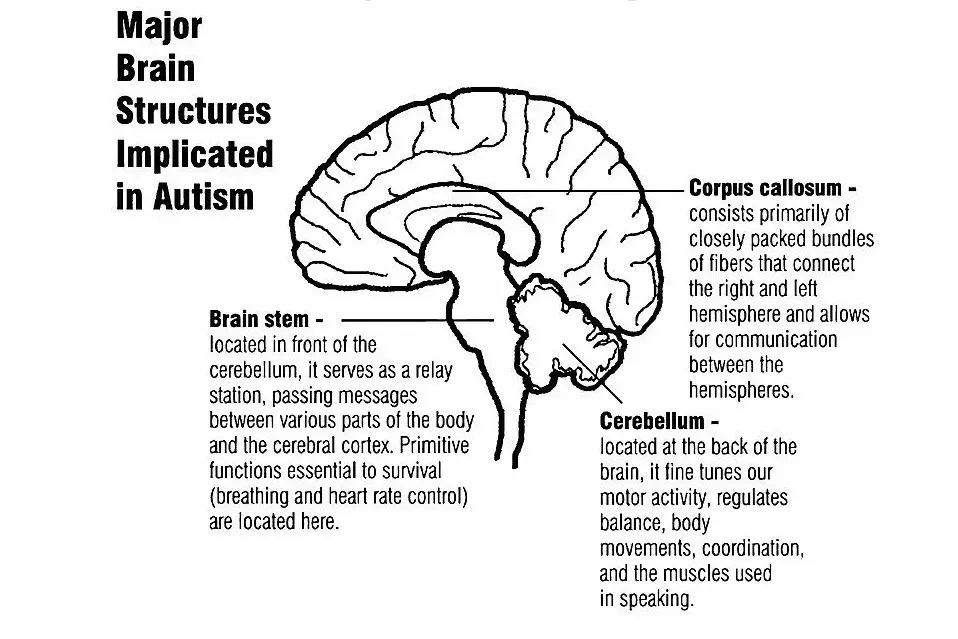

Medical technology innovations bring hope to children with cerebral palsy and autism, giving them a chance to regain health and grow up happily!

Conditions We Treat:cerebral palsy, autism, cerebellar atrophy, epilepsy, intractable epilepsy, cerebral hemorrhage, Parkinson's, Alzheimer's, sequelae of cerebral infarction, and various neurological disorders.